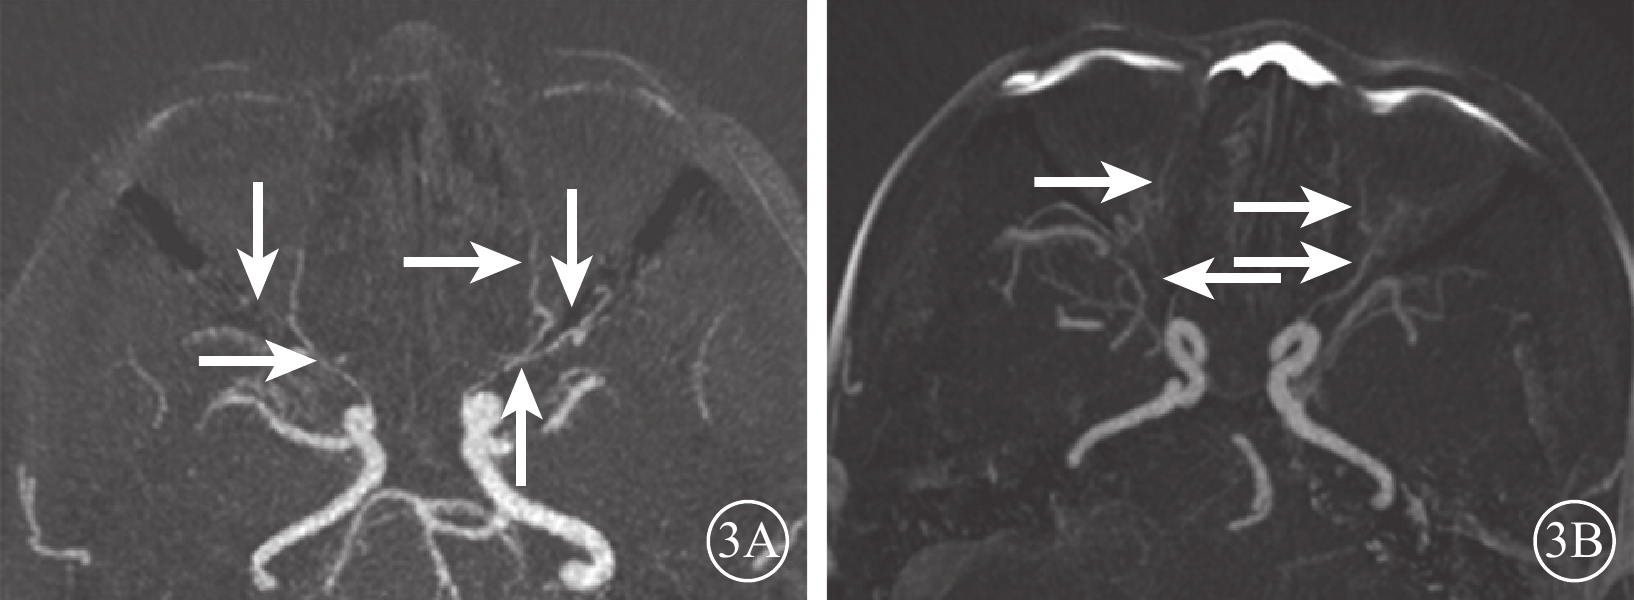

DR組72只眼中,眼動脈MRA 0級28只眼(38.9%);Ⅰ級28只眼(38.9%),其中眼動脈主干及其主要分支(鼻背動脈和淚腺動脈)顯影淺淡、外形變硬(圖2A)12只眼,眼動脈主干顯影正常、分支顯影中斷或不顯影14只眼;Ⅱ級16只眼(22.2%),其中眼動脈狹窄、僵硬伴分支顯影淺淡10只眼,分支顯影中斷或不顯影(圖2B)4只眼,眼動脈主干及其主要分支均不顯影2只眼。行CTA檢查的24只眼中,0級13只眼;Ⅰ級6只眼,其中眼動脈主干及其主要分支(鼻背動脈和淚腺動脈)顯影淺淡、管壁變硬(圖3A)4只眼,眼動脈主干顯影正常、分支不顯影2只眼;Ⅱ級5只眼,其中眼動脈主干伴分支明顯狹窄、僵硬(圖3B)3只眼,表現為眼動脈主干顯影分支不顯影2只眼。DR組眼動脈MRA、CTA分級一致性分析,Kappa值=0.86,一致性極強(表1)。DR組眼動脈MRA與對照組眼動脈MRA不同分級眼數比較,差異有統計學意義(Z=?5.74,P=0.000)。

圖3

DR患者CTA像。3A、3B. 分別為圖2A、2B患者CTA像。影像表現同MRA

圖3

DR患者CTA像。3A、3B. 分別為圖2A、2B患者CTA像。影像表現同MRA

DR組72只眼中,眼動脈MRA 0級28只眼(38.9%);Ⅰ級28只眼(38.9%),其中眼動脈主干及其主要分支(鼻背動脈和淚腺動脈)顯影淺淡、外形變硬(圖2A)12只眼,眼動脈主干顯影正常、分支顯影中斷或不顯影14只眼;Ⅱ級16只眼(22.2%),其中眼動脈狹窄、僵硬伴分支顯影淺淡10只眼,分支顯影中斷或不顯影(圖2B)4只眼,眼動脈主干及其主要分支均不顯影2只眼。行CTA檢查的24只眼中,0級13只眼;Ⅰ級6只眼,其中眼動脈主干及其主要分支(鼻背動脈和淚腺動脈)顯影淺淡、管壁變硬(圖3A)4只眼,眼動脈主干顯影正常、分支不顯影2只眼;Ⅱ級5只眼,其中眼動脈主干伴分支明顯狹窄、僵硬(圖3B)3只眼,表現為眼動脈主干顯影分支不顯影2只眼。DR組眼動脈MRA、CTA分級一致性分析,Kappa值=0.86,一致性極強(表1)。DR組眼動脈MRA與對照組眼動脈MRA不同分級眼數比較,差異有統計學意義(Z=?5.74,P=0.000)。

圖3

DR患者CTA像。3A、3B. 分別為圖2A、2B患者CTA像。影像表現同MRA

圖3

DR患者CTA像。3A、3B. 分別為圖2A、2B患者CTA像。影像表現同MRA